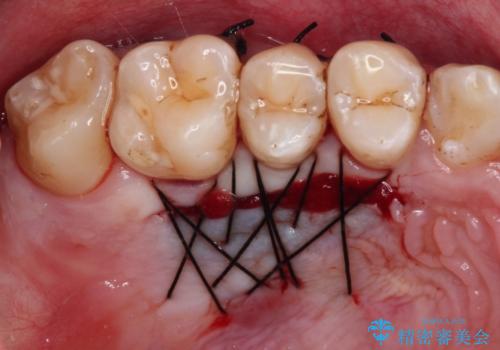

- 下顎犬歯の歯肉退縮を気にして来院された患者様です。

歯磨きの際にしみるとのことで、歯肉移植による根面被覆を行うこととしました。

歯肉移植により根面被覆が達成されるとともに、歯肉が厚みを増したことで、今後の歯肉退縮リスクを軽減させることができました。